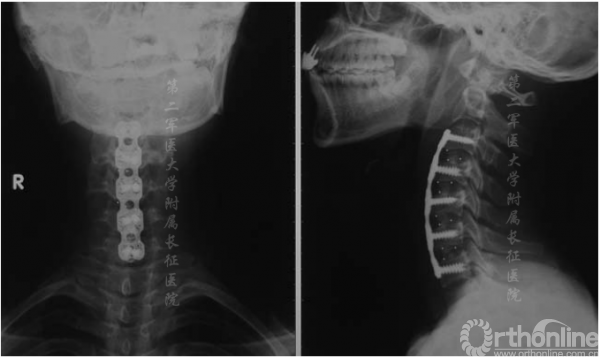

图4.术后6个月x线片显示内固定位置满意,椎体对位齐和骨融合

手术后6个月内,JOA评分从术前平均14分提高到术后平均16.3分。所有患者的JOA恢复率均较为满意。内在肌肉、腕部屈肌和伸肌以及二头肌和三头肌的肌力平均提高了1级。骨移植完全融合(图4),颈椎管容积和颈矢状位满意(图5)。没有发生与手术有关的并发症。